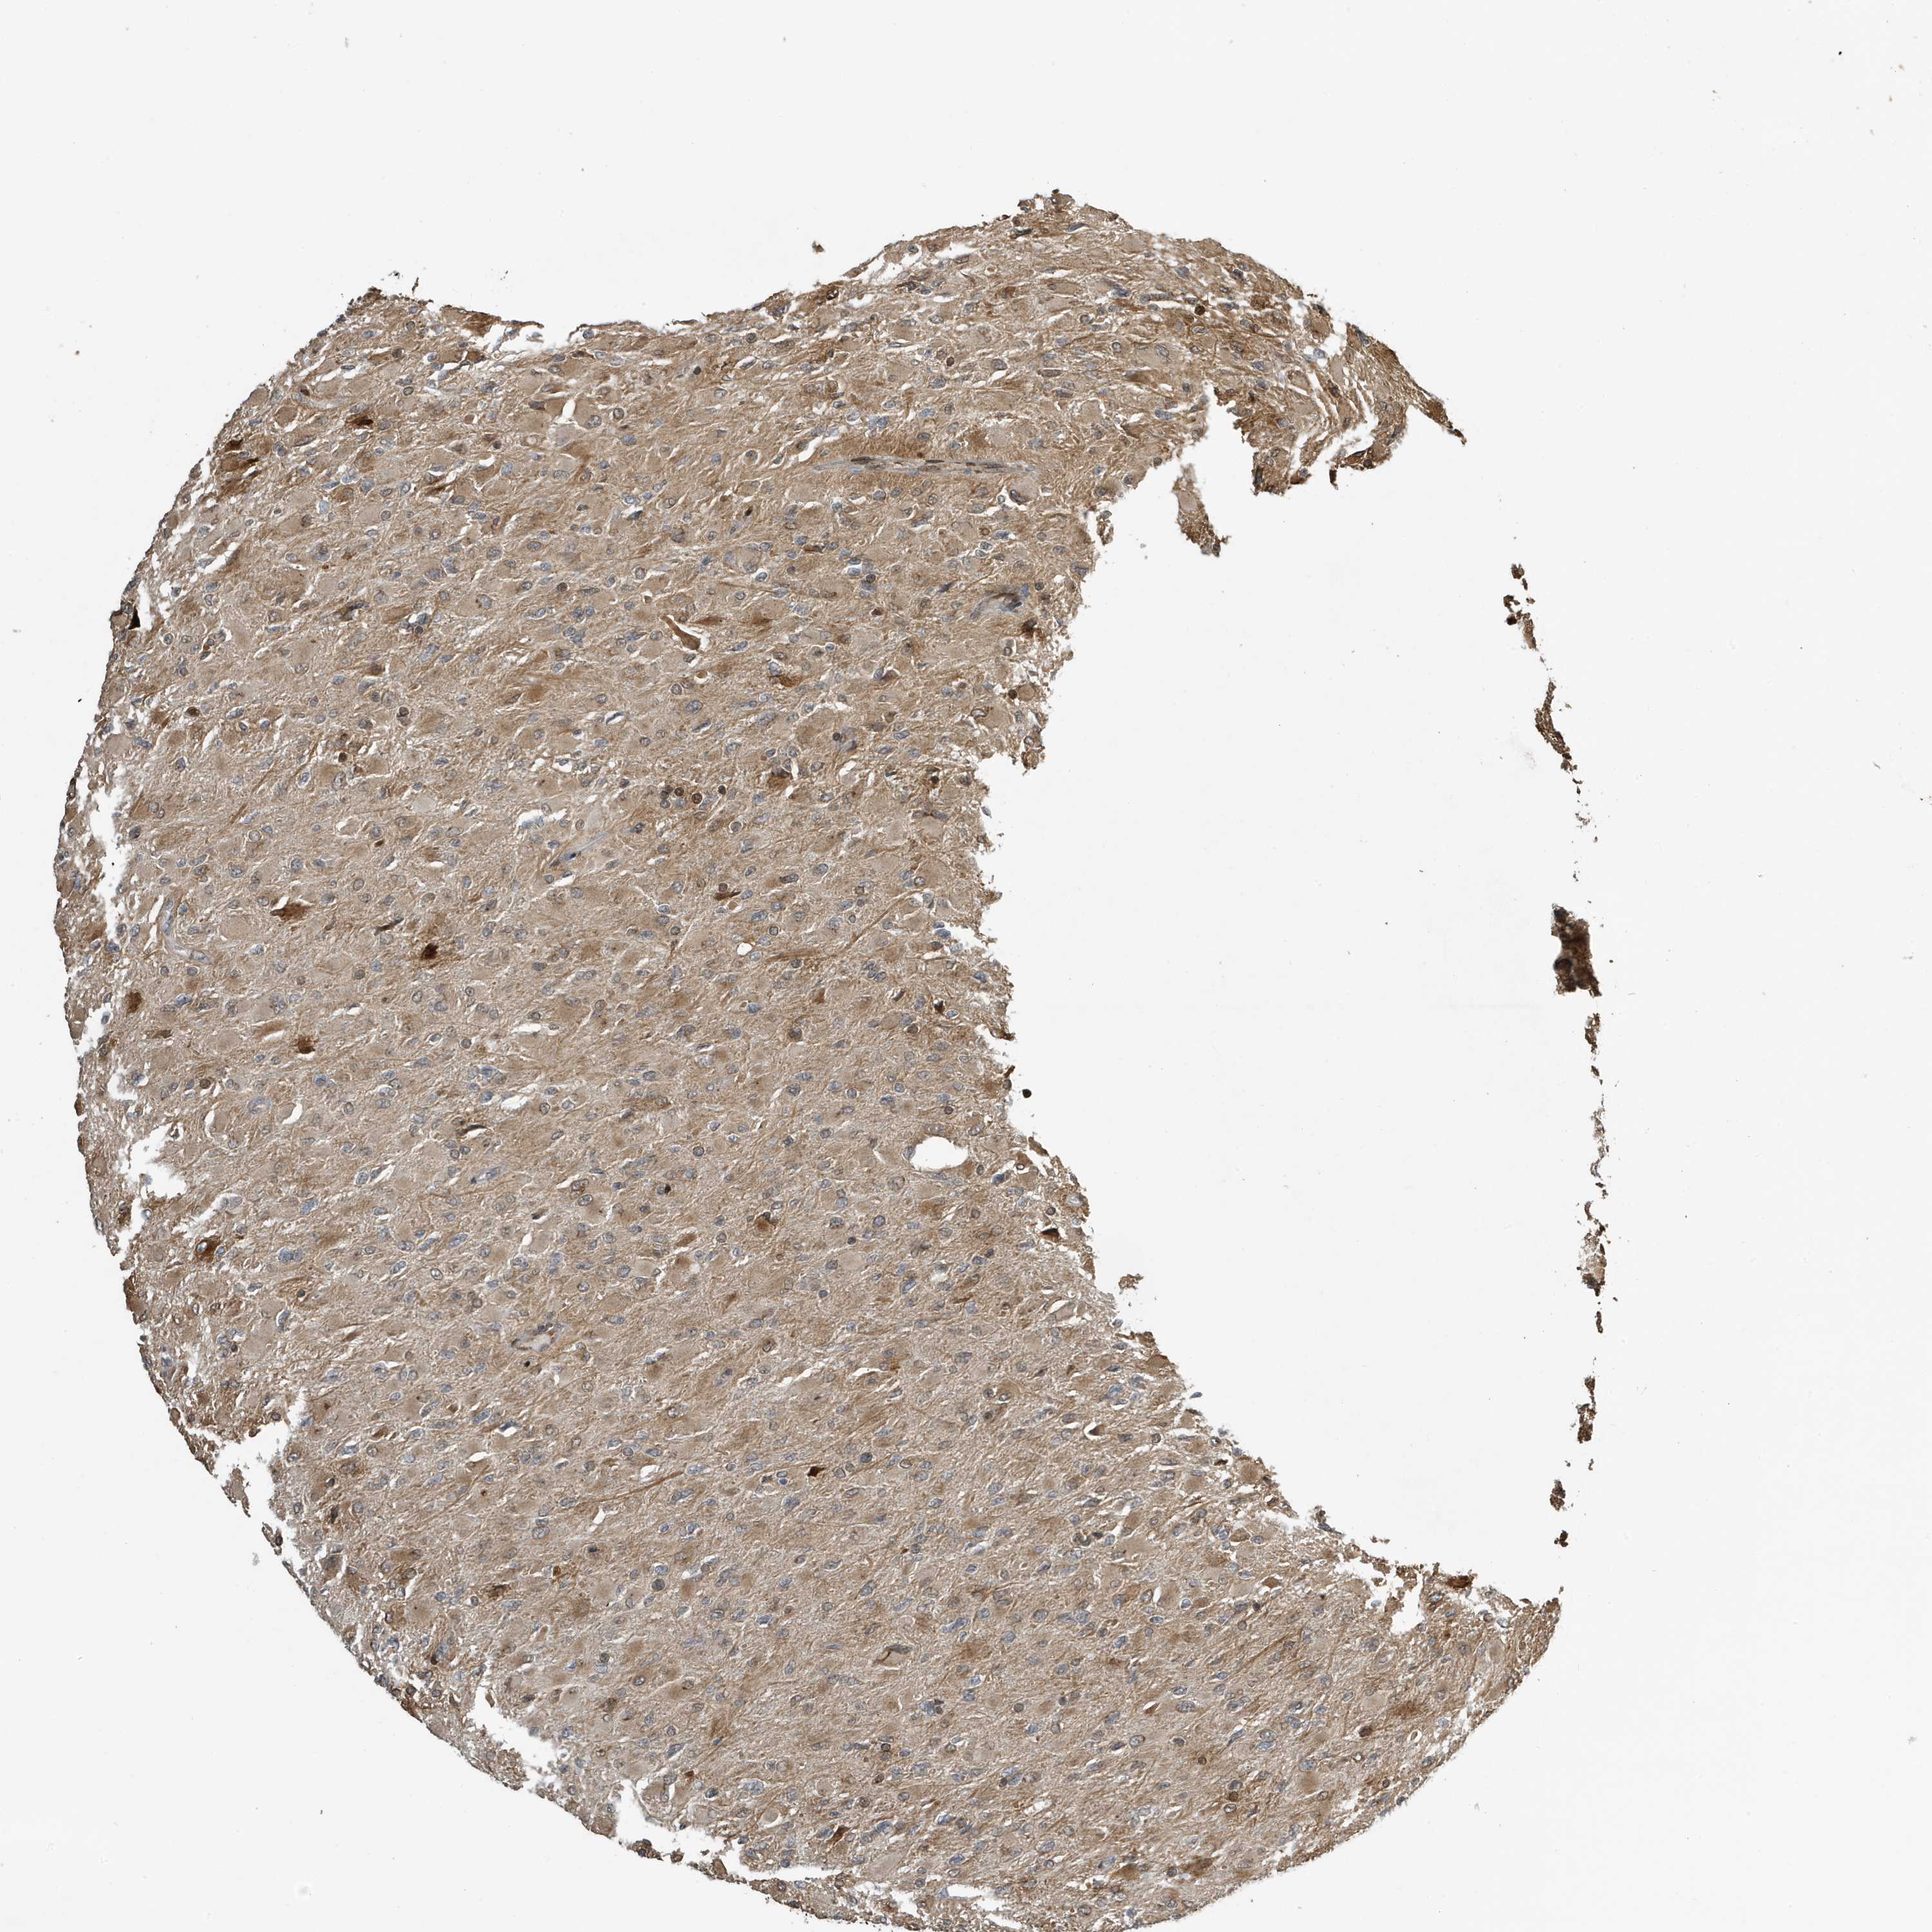

GLIOMA - Protein expressioni

A mouse-over function shows sample information and annotation data. Click on an image to view it in a full screen mode. Samples can be filtered based on level of antibody staining by selecting one or several of the following categories: high, medium, low and not detected. The assay and annotation is described here.

Note that samples used for immunohistochemistry by the Human Protein Atlas do not correspond to samples in the TCGA dataset.

Antibody stainingi

Antibody staining in the annotated cell types in the current human tissue is reported as not detected, low, medium, or high, based on conventional immunohistochemistry profiling in selected tissues. This score is based on the combination of the staining intensity and fraction of stained cells.

Each image is clickable and will lead to virtual microscopy that enables deeper exploration of all samples and also displays staining intensity scores, fraction scores and subcellular localization as well as patient and tissue information for each sample.

Antibody CAB034070

Staining

High

Medium

Low

Not detected

Intensity

Strong

Moderate

Weak

Negative

Quantity

>75%

75%-25%

<25%

None

Location

Nuclear

Cytoplasmic/membranous

Cytoplasmic/membranous,nuclear

Glioma, malignant, High grade

Glioma, malignant, Low grade